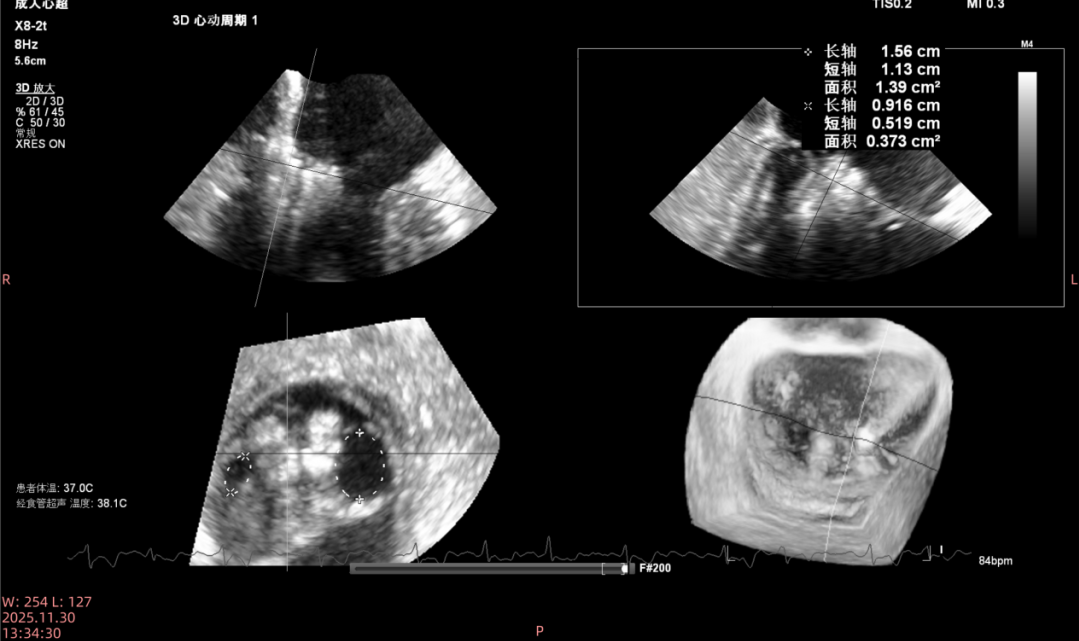

撤出系统后复查食道超声示: 瓣叶钳夹稳定度良好,脱垂消失,未见明显反流,测量平均压差3mmHg,肺静脉逆流消失。达到预期介入效果,手术成功。

平均压力梯度

术后瓣膜的开口面积

撤出系统后复查食道超声示: 瓣叶钳夹稳定度良好,脱垂消失,未见明显反流,测量平均压差1mmHg,肺静脉逆流消失。达到预期介入效果,手术成功。